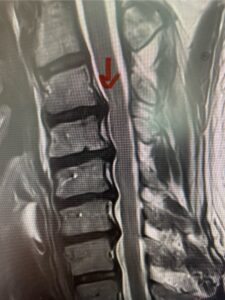

The next patient is a 54 year-old male who presents with 3 years of neck pain with associated numbness and tingling of his extremities. Patient had had physical therapy, chiropractic care, and epidural steroid injections with no significant relief. The patient on exam had weakness in a long tract distribution on the left. MRI revealed four level disc disease from C3-4 to C6-7 with a moderate kyphosis and cord compression and signal change at C3-4 (Fig. 9). Because of the kyphotic deformity it was decided to perform a four-level anterior cervical discectomy and interbody cage at each segment as well as plate. The patient had significant osteophyte disease at each level which required a high-speed drill to shave down the osteophytic disease and remove and decompress the foramina with fine Kerrison. Intraoperative imaging revealed good placement of the cages and plate at each level (Fig. 10). The patient had good relief of his preoperative symptoms.

Fig. 9a Sagittal T2-weighted cervical MRI demonstrating severe upper cervical spinal cord compression secondary to C2 anterior subluxation on C3 with development of thickened posterior degenerative material (red arrow)

Fig. 9b

Fig. 9c